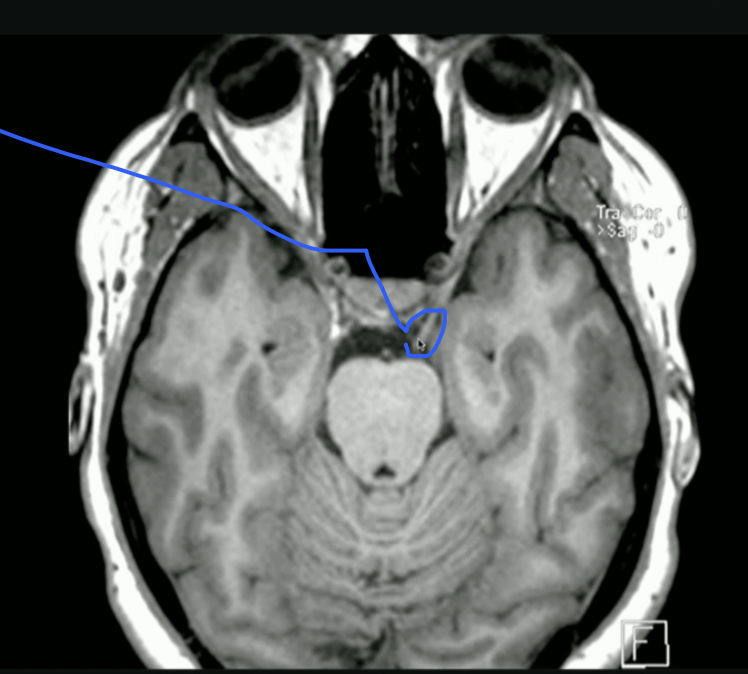

<p>What is the mouse Pointing to? + What does it create?</p>

What is the mouse Pointing to? + What does it create?

• Anterior Horn of Lat. Ventricle

• Houses Choroid Plexus → Creates CSF

• IF: Caudate nucleus swells → Impacts Lat. Ventricle → Huntingtons Disease